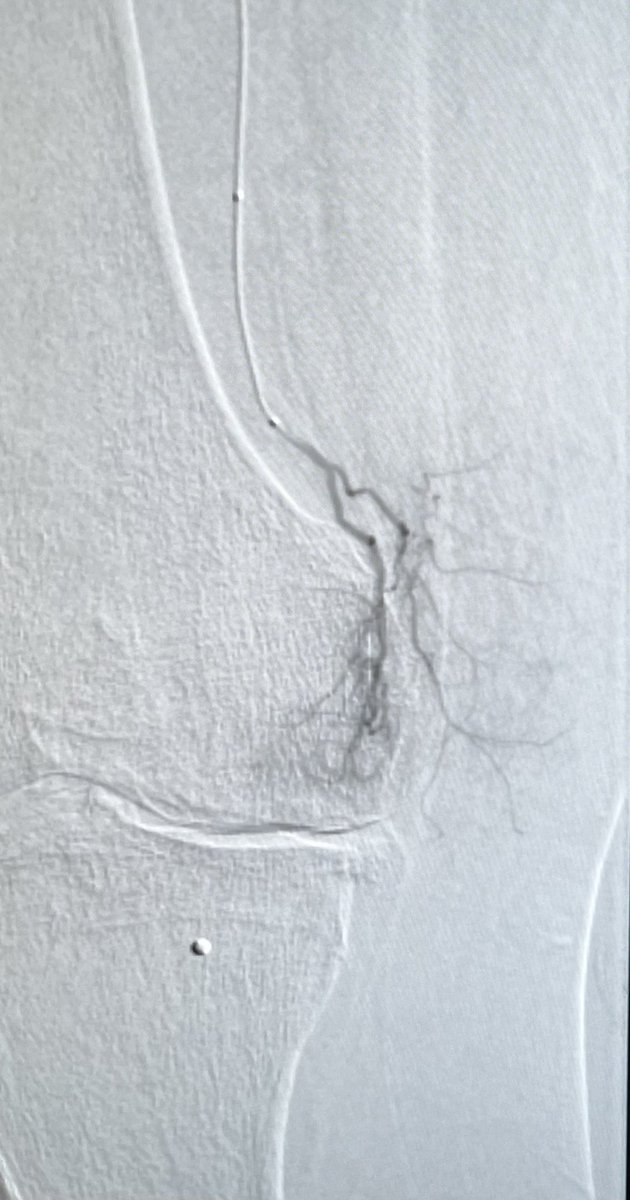

@LCasadaban

Leigh Casadaban, MD

4 years

Genicular Artery Embolization for knee osteoarthritis. No skin mottling or ulcers. @IrColorado